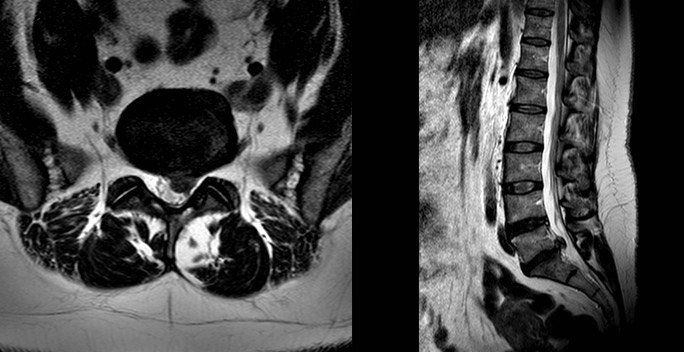

What does a disc prolapse look like?

The pictures above are of an MRI scan showing a prolapsed disc. The dark oval structure in the centre is a disc and the bulge coming off the base is the “prolapsed disc” protruding into the spinal canal on the cross- section view. In the image on the right the disc prolapse can be seen as a circle behind the spinal bones. When it touches a nerve you will feel pain radiating from your back down the leg and this is known as sciatica.